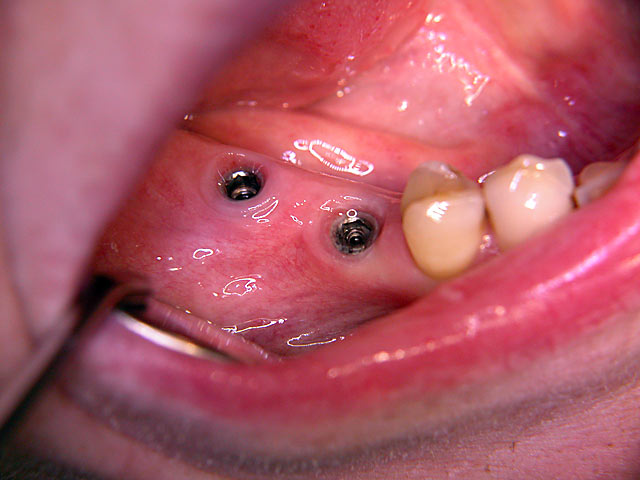

Die folgenden Patientenfälle sollen Ihnen einen Einblick in die Möglichkeiten der modernen Implantation geben.

Implantation mit fester Brücke: